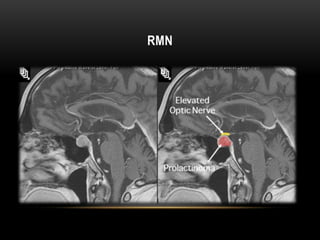

DIAGNOSTICO

• Con la sintomatología ya mencionada el médico debe tener

sospecha de una prolactinoma pero esto solo es confirmado

mediante exámenes complementarios

RMN